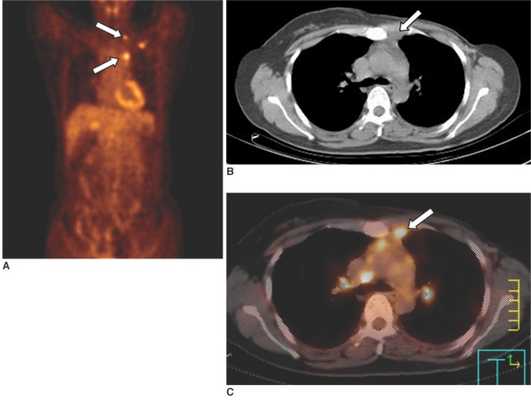

Опухоль левого легкого с частичным некрозом и деструкцией ребер. Визуализируются два метастаза в подключичных лимфоузлах и в мышцах (стрелки), которые на КТ не видны. Необходимо выполнить трансторакальную биопсию той части опухоли, которая расположена в периферических отделах, чтобы получить образец жизнеспособных тканей.

Метастазы в лимфоузлы средостения у женщины, 10 месяцев назад перенесшей модифицированную радикальную левостороннюю мастэктомию. А: на ПЭТ определяются множественные участки гиперметаболизма РФП в верхних отделах грудной клетки слева. В: на КТ визуализируется небольшой участок мягкотканной плотности в переднем средостении (отмечен стрелкой). В: на ПЭТ-КТ обнаружено, что мяготканный участок в переднем средостении, выявленный при КТ, соотносится с зоной гиперметаболизма ФДГ, что позволяет предположить метастазы во внутригрудные лимфатические узлы.